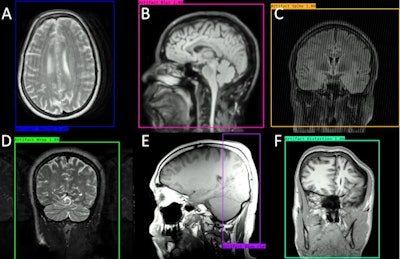

The model was trained on 4,606 brain images made up of three image contrasts (T1-weighted, T2-weighted, and FLAIR) and three imaging planes (axial, sagittal, and coronal). These images were then augmented to produce six common image artifacts: motion, wrap, blurring, bias field, RF spike, and geometric distortion.